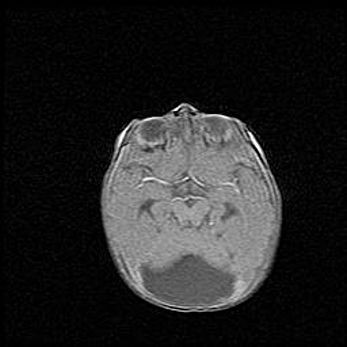

Множественные кисты обоих полушарий головного мозга, наибольшая из них в правой затылочной области. Ассиметричная атрофическая гидроцефалия.

Возраст: 7 месяцев

Вес: 5660 г

Пол: мужской

Окружность головы: 41,5 см

Срок гестации: 28-29 недель

Кисты головного мозга развиваются в результате многоочаговых некрозов вещества мозга и возникают вследствие перенесенной перинатальной инфекции, менингитов, энцефалитов, асфиксии, родовой травмы, расстройств мозгового кровообращения различного генеза. Образованию кист в веществе головного мозга плодов и новорожденных способствуют такие факторы, как высокое содержание в нем воды, недостаточная (или отсутствие) миелинизация и слабая астроглиальная реакция на повреждение.

Кисты могут сочетаться с гидроцефалией и другими поражениями головного мозга.